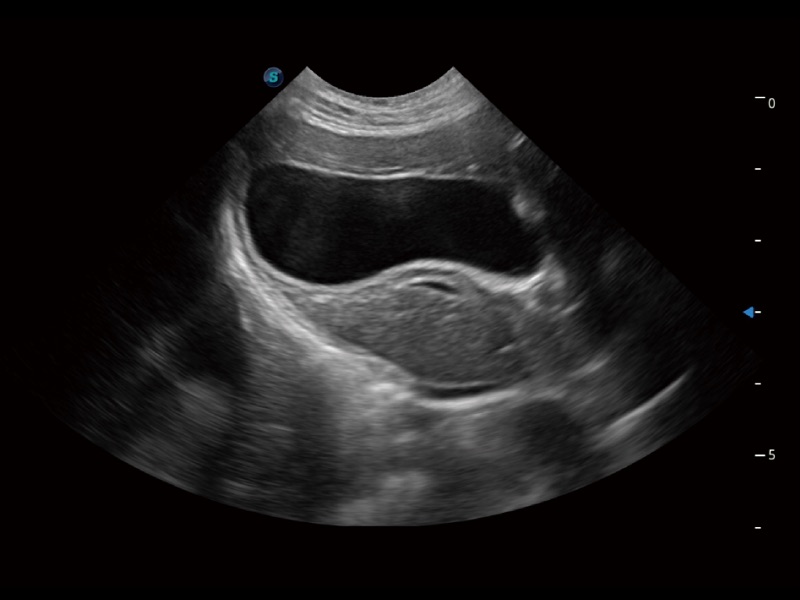

(猫)胆囊